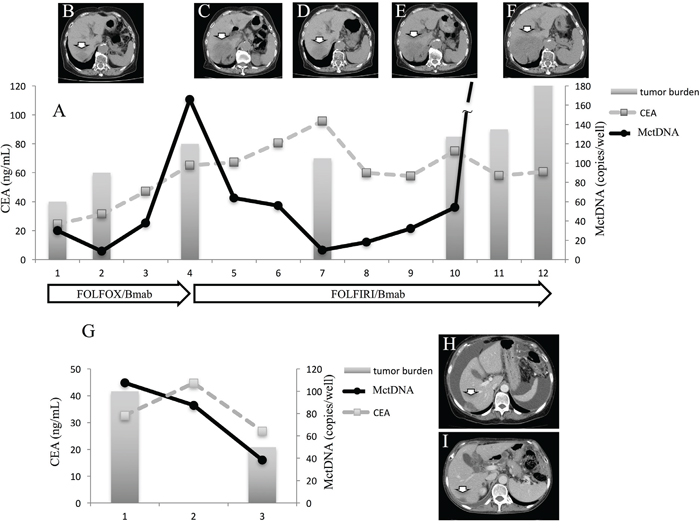

In 29 patients with the MT, MctDNA was detected in 23 patients (79.3%) (Figure 1A). Among 18 patients who underwent second-line or subsequent treatment lines, MctDNA was detected in 17 patients (94.4%). Details of the clinical course of these 29 patients is shown in Table 1. The median value of MctDNA was 64.0 copies/well (3.2–45800) for the number and 10.10% (0.26–93.60) for the ratio in these 29 patients (Figure 1B and 1C). Comparing progression-free survival (PFS) of the first-line treatment between patients with MctDNA and without, there was a significant difference in PFS (Figure 2A), with a worse outcome in patients with MctDNA (22.0 vs 3.0 months, p = 0.0007). Most patients showed a continuous change with increasing MctDNA (Figure 3A and 3C). Four patients had a stable MctDNA level, suggesting a long stable disease (Figures 3B and 4A), and two patients showed a quick decrease in MctDNA with shrinkage of tumors in response to treatment (Figure 3D and Figure 4G).

Figure 4: Clinical course of a mCRC patient with multiple liver metastases with a long stable disease (A and G) and computed tomography (CT) (B–F). A 75-year-old woman with multiple liver metastases is denoted as patient 1. She was treated with FOLFOX + bevacizumab for the first-line treatment. (A) and (B) show CT images before and after treatment with FOLFOX + bevacizumab. Increased levels of MctDNA were observed before radiological progression (B). FOLFIRI + bevacizumab was administrated as the second-line treatment. The tumor did not change in size (C, D, and E) and levels of MctDNA were stable for a time with the second-line treatment. Progression-free survival of 6 months was achieved with stable levels of MctDNA (A), followed by progression detected by CT (F). A 66-year-old woman with multiple liver metastases and ascites is denoted as patient 12. She was treated with XELOX + bevacizumab for the first-line treatment. (H) and (I) show CT images before and after treatment with XELOX + bevacizumab. The tumor shrank and levels of MctDNA decreased (I). Arrow shows liver metastasis. CEA: carcinoembryonic antigen.

Clinical course of two patients who showed a spike in elevation in mutated circulating tumor DNA

A spike in elevation was seen in six patients treated with anti-VEGF antibody or TAS-102. Although detection of MctDNA was generally seen in patients with disease progression, a spike in elevation of MctDNA was observed in patients who likely responded to drug treatments, followed by a quick disappearance. A patient who showed a drug response with a spike in elevation is shown in Figure 5. Despite there being no change in tumor size, tumors did show changes in morphology induced by TAS-102 + bevacizumab as the second-line treatment. It is reported that patients with a change in morphology show as good a drug response as those patients with a change in size, similar to a partial response and a complete response, estimated using Response Evaluation Criteria in Solid Tumours (RECIST) in not only colorectal cancer but other types of tumors such as gastrointestinal stromal tumors [23, 24, 25]. Interestingly, this patient also showed a change in tumor morphology with first-line treatment using XELOX + bevacizumab. There were some patients with a decline in MctDNA, suggesting recovery of drug sensitivity, who were then treated with re-introduction of anti-EGFR antibody. Figure 6 shows a representative image of a patient who responded to re-introduction of anti-EGFR antibody. The patient achieved a partial response and 7 months PFS with the sixth-line treatment.

Figure 5: Clinical course of a mCRC patient with multiple liver metastases (A) with morphological changes seen with computed tomography (CT) (B–G) and a spike in elevation in MctDNA. A 60-year-old male with multiple liver metastases is denoted as patient 76. He was treated with XELOX + bevacizumab as the first-line treatment. (B) and (C) show CT images before and after treatment with XELOX + bevacizumab. A change in tumor morphology from heterogeneous to homogeneous low-attenuation was seen in the liver metastases four cycles after treatment with XELOX + bevacizumab despite no change in tumor size. The patient found XELOX + bevacizumab treatment difficult because of severe adverse events and he underwent surgery (right lobectomy for the main tumor and partial resection for other multiple metastases). Soon after surgery, a recurrent liver tumor was found along with increased levels of carcinoembryonic antigen (CEA). Chemotherapy was suggested but the patient refused because of the previous severe adverse events with the first-line treatment. TAS-102 + bevacizumab was then suggested because TAS-102 did not show severe adverse events. Soon after treatment with TAS-102 + bevacizumab, CEA drastically decreased and liver tumors showed morphological changes, which were also seen with the first-line treatment. Additionally, a spike in elevation in MctDNA was observed during this drug response.

KRAS monitoring identified continuous, intermittent, and transient changes in MctDNA. Continuous detection of MctDNA was frequently seen in MT patients, whereas intermittent detection was more often seen in WT patients. These changes may be associated with the different levels of MctDNA observed between WT and MT patients. In WT patients treated with anti-EGFR antibody, initial detection of MctDNA was likely prior to radiological disease progression (Figure 1D) [10, 9, 19]. Although detection of MctDNA was generally seen in patients with disease progression, transient changes with a spike in elevation were seen in patients in association with the drug response (Figures 3H and 5). One patient showed a transient change with a spike in elevation during treatment with TAS-102, followed by disease progression (Figure 6). MctDNA then disappeared in this patient and anti-EGFR antibody was reintroduced, which achieved a partial response and a long PFS of 7 months with the fifth-line treatment. The results suggest that the later treatment lines had a significant effect on improving the outcome for this patient. The rapid disappearance may have been induced by a delayed drug response to TAS-102 [34]. TAS-102 has a unique mechanism and works by being integrated into the DNA of the tumor cells. Such a process requires some time before an effect on the tumor is observed [35, 36]. The spike in elevation followed by disease progression may indicate a delayed drug response of TAS-102 and contributing effects associated with anti-EGFR antibody.